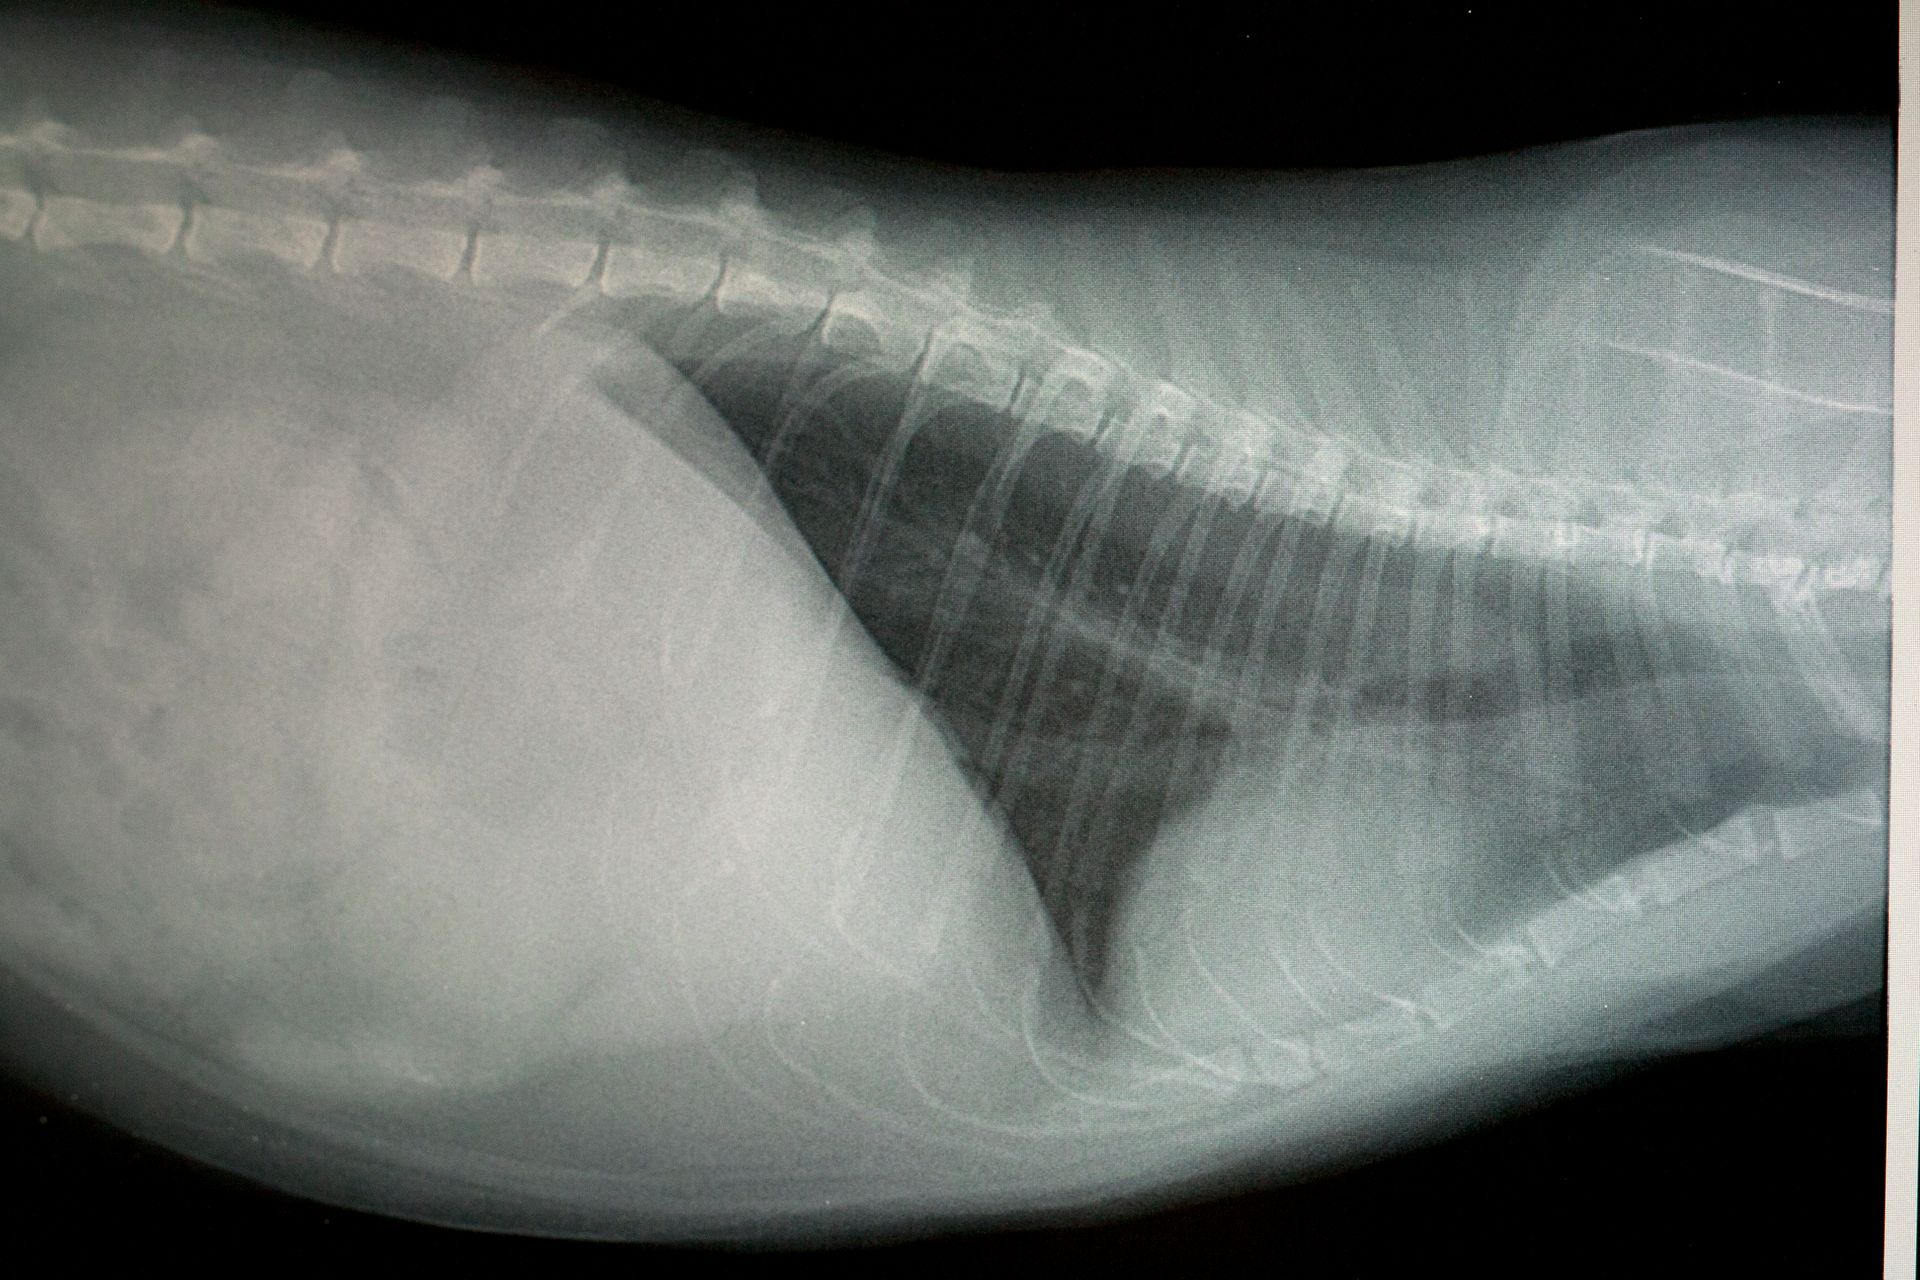

Michelle Gerster documents the work of Cats on Call, a veterinary hospital that focuses on domestic cats in the Portland area.